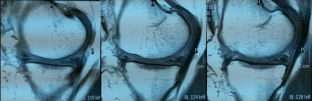

Fig. 2